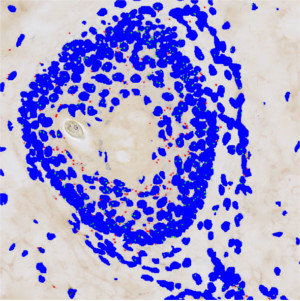

Figure 3

Results of analysis with the APP: “02 Analyze”. Nuclei inside the dermis and epidermis regions are labeled blue, whereas probes inside the nuclei are labeled green and probes outside the nuclei red.

The first image processing step involves an automated detection of the dermis and epidermis, i.e. the regions of interest (ROI) (see FIGURE 2). The nuclei and probes are subsequently detected inside these ROIs (see FIGURE 3, 5 and 7). A polynomial blob filter that enhances the probes’ features is used for the identification of the probes, whereas the haematoxylin color-deconvolution band is used for the identification of nuclei. The initial classification of nuclei and probes is managed with a postprocessing protocol to firstly refine the detection of nuclei and probes, and secondly to qualitatively determine if probes are covered by nuclei or not for the final probe quantification. For each tissue type, i.e. dermis and epidermis, probes are counted and categorized as either covered by nuclei or as separate from nuclei.